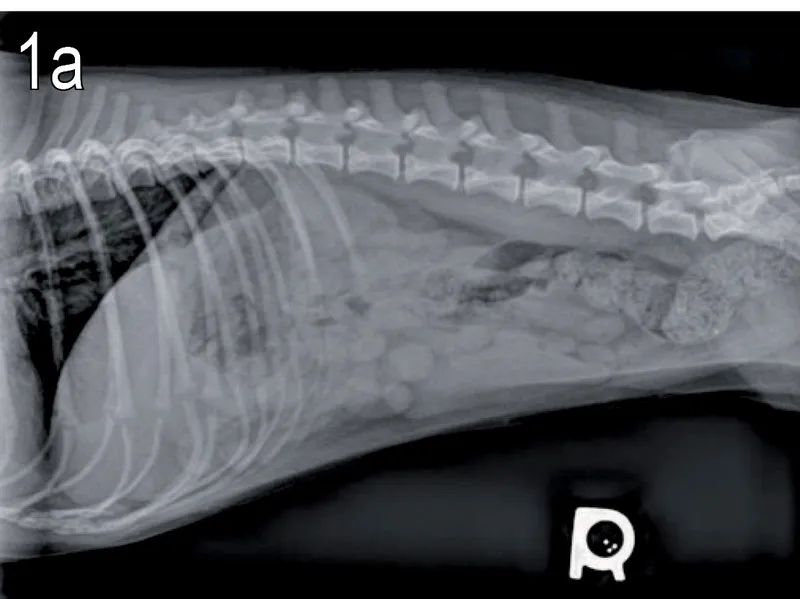

Jednak jeśli pies zjadł dużą, twardą kość, zwłaszcza gotowaną, lub jeśli pojawią się jakiekolwiek z wymienionych wyżej niepokojących objawów, natychmiast skontaktuj się z weterynarzem. Nie czekaj! Czas jest kluczowy w przypadku potencjalnej perforacji czy niedrożności. Lekarz weterynarii może zalecić badania obrazowe (RTG, USG), aby ocenić położenie kości i podjąć odpowiednie kroki, takie jak leczenie zachowawcze, endoskopia lub interwencja chirurgiczna.